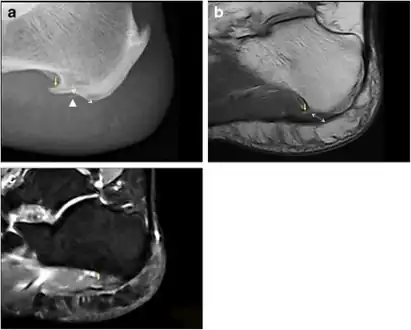

Spur outgrowths can be detected through physical exam followed by a lateral foot x-ray.

a) Plantar calcaneal spur at the origin of intrinsic muscles of the foot b) MRI confirms the presence of a calcaneal spur c) bone marrow oedema in the calcaneal spur

Inferior calcaneal spur